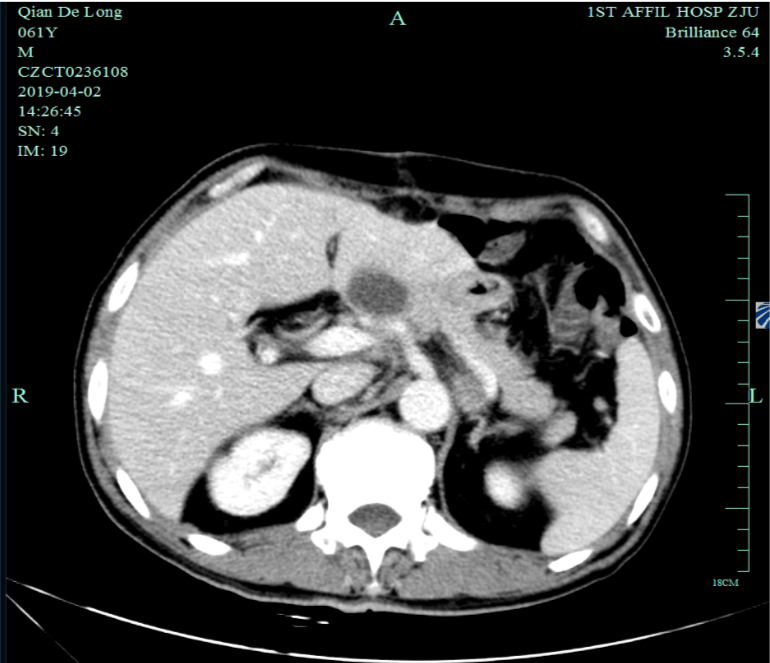

入我院后全面进行评估(2019.4):全腹部CT平扫+增强评估提示腹膜后,胰腺周围多发淋巴结增大,淋巴结转移考虑。

2019-4-2至2019-6-5行SOX+赫赛汀 q3w 4周期联合化疗:具体为奥沙利铂220mgD1、替吉奥3# BID D1-14、赫赛汀400mg(首次)+300mg。